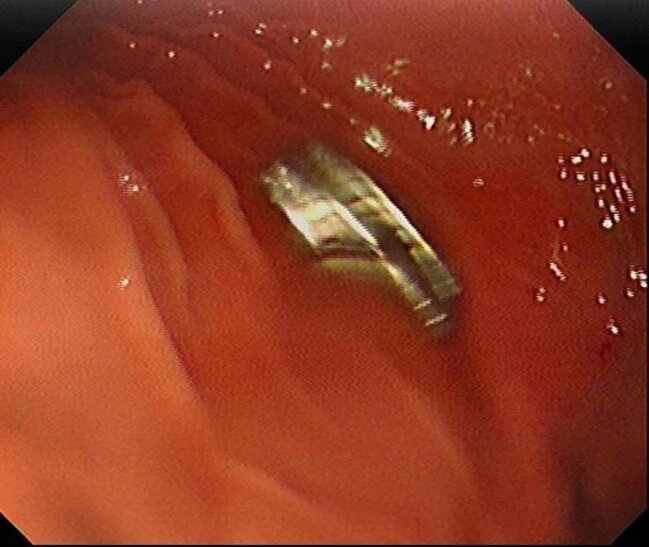

Fırat Universitetinin Uşaq Qastroenterologiyası, Hepatologiya və Qidalanma kafedrasının müdiri Prof.Dr.Yaşar Doğan endoskopik üsulla uşağın qida borusuna ilişib qalmış 19 maqniti çıxarıb.

Maqnitlər uzun müddət qida borusunda ilişib qalıb, yemək borusu və mədə girişində zədələr yaranıb.